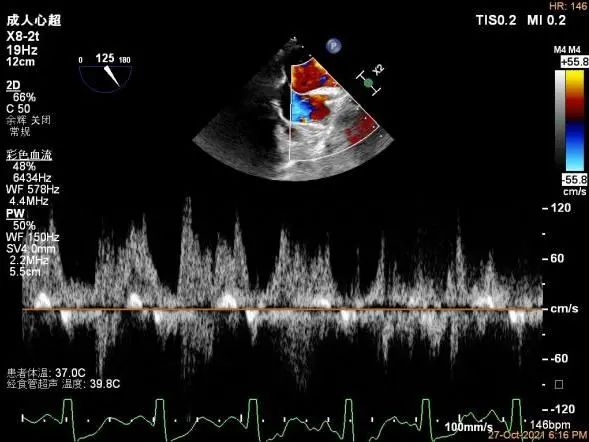

夹子放置后二尖瓣口平均跨瓣压差:1mmHg

肺静脉血流频谱恢复正向

夹子脱钩后,最终仅少量残余分流